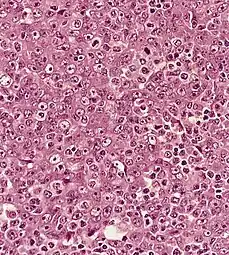

Micrograph showing a nasopharyngeal carcinoma positive for Epstein-Barr virus-encoded small RNAs (EBER).

Type 3 is most commonly found among younger children and adolescents, with a few type 2 cases. Both type 2 and 3 have been found to be associated with elevated levels of Epstein-Barr virus titers, but not type 1. Additionally, type 2 and type 3 may be followed with an influx of inflammatory cells, including lymphocytes, plasma cells, and eosinophils, generating the term lymphoepithelioma.[15]

Nasopharyngeal carcinoma, also known as nasopharyngeal cancer, is classified as a malignant neoplasm, or cancer, arising from the mucosal epithelium of the nasopharynx, most often within the lateral nasopharyngeal recess or fossa of Rosenmüller (a recess behind the entrance of the eustachian tube opening). The World Health Organization classifies nasopharyngeal carcinoma in three types, in order of frequency: Non-keratinizing squamous cell carcinoma; keratinizing squamous cell carcinoma; and basaloid squamous cell carcinoma.[16] The tumor must show evidence of squamous differentiation, with the non-keratinizing type (also known as lymphoepithelioma) the tumor most strongly associated with Epstein-Barr virus infection of the cancerous cells.[17]